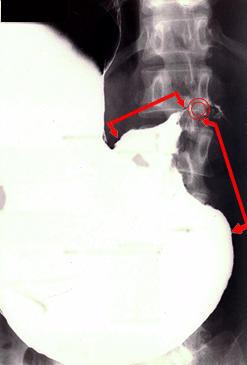

Criteria of Hist.ClassificationMalignant epithelial tumor/Adenocarcinoma

LocationStomach/Antrum

Technique, MethodX-ray

Macroscopic TypesType 3 Ulcerated type with infiltration/

Size40 -

Depth of Tumor Invasionserosa (adventitia)